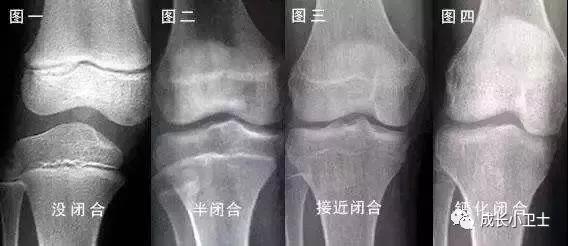

孩子到了醫(yī)院,進行各項檢查可以幫助我們更進一步的了解長不高的原因。各項檢查包括血、尿檢查,肝、腎功能檢測和甲狀腺激素、生長激素、生長因子、腎上腺功能檢測,這些檢查對于評價孩子的一般健康狀況和內(nèi)分泌腺體功能非常重要。女孩還要做染色體核型分析,因為有一種染色體疾病叫做Turner綜合癥,特別鐘情于女孩子,不僅會影響身高,還會阻礙青春期的發(fā)育。同時,需對左手掌、指進行X光射線照片,以了解骨齡,判斷骨骺閉合的程度和生長潛力。根據(jù)情況,有的孩子還需要進行頭顱的MRI檢查,以排除先天發(fā)育異;蚰[瘤的可能性。

孩子年齡越小,骨骺軟骨層增生及分化越活躍,生長的潛能和空間越大。一旦骨骺接近或已經(jīng)閉合,就耽誤了最佳治療時機,任何方案均無法得到滿意效果。